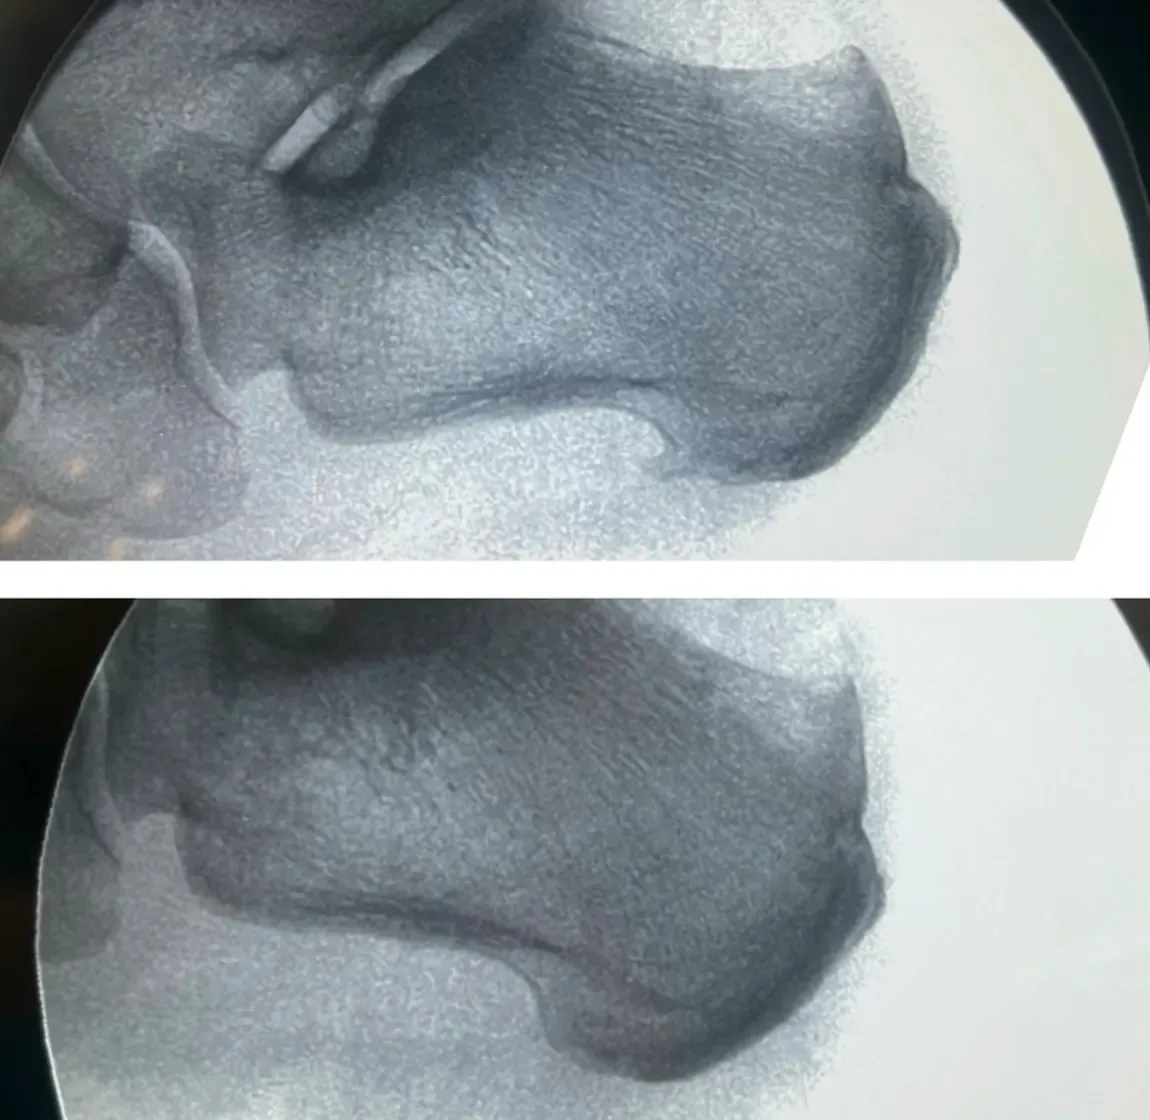

Un espolón calcáneo es simplemente una calcificación ósea normal que se forma en la inserción de la fascia plantar en el hueso calcáneo. Contrario a la creencia popular, no es una patología sino una adaptación natural del hueso ante las tensiones repetitivas.

- La presencia en radiografía NO predice dolor

¿Te han hecho solo una radiografía para diagnosticar tu dolor de talón? Las radiografías únicamente muestran estructuras óseas, pero el dolor proviene de tejidos blandos que no son visibles en este tipo de imagen.